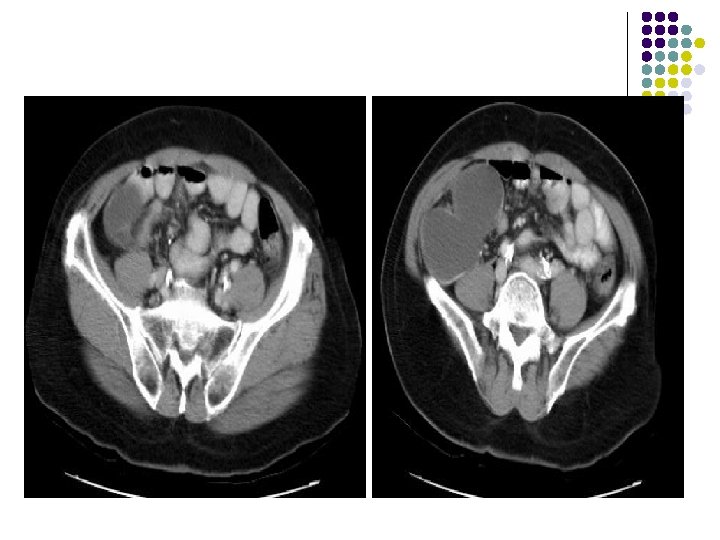

CT: l There is a bilobed, thin-walled, fluidattenuation mass in the right iliac fossa. l There is some calcification in the posterior wall of this lesion. l l The mass abuts the cecum The appendix is not visualized separately.

Diagnosis: l MUCOCELE OF APPENDIX

DISCUSSION l It is a rare condition. 25% of mucoceles are asymptomatic. l Mucocele is a descriptive term indicating that the appendix is dilated due to intraluminal mucinous secretions. l It develops slowly and appendix may become quite large. l l CAUSES: Obstructing lesions…. post-appendicitis scarring, carcinoma of appendix, cecum or ascending colon and appendiceal volvulus. Rupture of a mucocele leads to pseudomyxoma peritonei.

IMAGING FEATURES l Plain abdominal film: A well-defined right lower quadrant mass. l Contrast enema: Smooth indentation of the medial aspect of the cecum & non-opacification of the appendix. l Ultrasound: Completely anechoic or hypoechoic with variable internal echogenicity and Whorled appearance is characteristics due to internal contents May have posterior acoustic enhancement. with variable wall thickness and calcification.

l CT: Cystic structures with thin well-defined walls. Contents are usually of homogenous fluidattenuation. Calcification may be noted in the wall. l MR: If the mucocele contains predominantly fluid it will have low signal intensity on T 1 weighted images and high signal intensity on T 2. If, however, the mucocele contains a significant amount of mucin, it will appear hyperintense on both T 1 and T 2 weighted images.